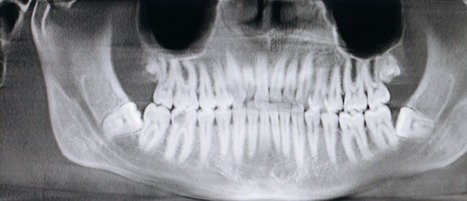

Types of Dental X-Rays

There are several types of dental X-rays, each serving a specific purpose in diagnosing and monitoring oral health.

- Bitewing X-rays are commonly used to detect decay between teeth and check the fit of dental restorations like crowns and fillings.

- Periapical X-rays provide a detailed view of the entire tooth, from the crown to the root, and are often used to diagnose issues in the root structure or surrounding bone.

- Panoramic X-rays capture the entire mouth in a single image, including the teeth, jaw, and surrounding structures, making them ideal for assessing impacted teeth, planning orthodontic treatment, or detecting bone abnormalities.

- Occlusal X-rays offer a view of the floor or roof of the mouth, helping to track the development of teeth in children or detect abnormalities like cysts or tumors. Each type of X-ray plays a key role in ensuring comprehensive dental care.